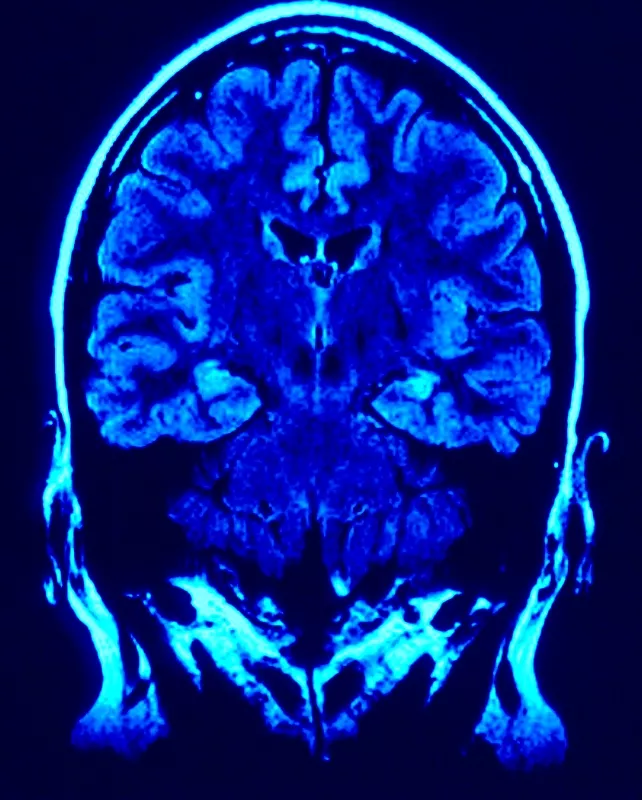

Az agy frontalis metszete képalkotó eszközzel